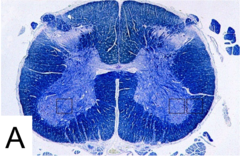

Myelin stain

Front

stains myelin a deep blue (white matter!)

Back